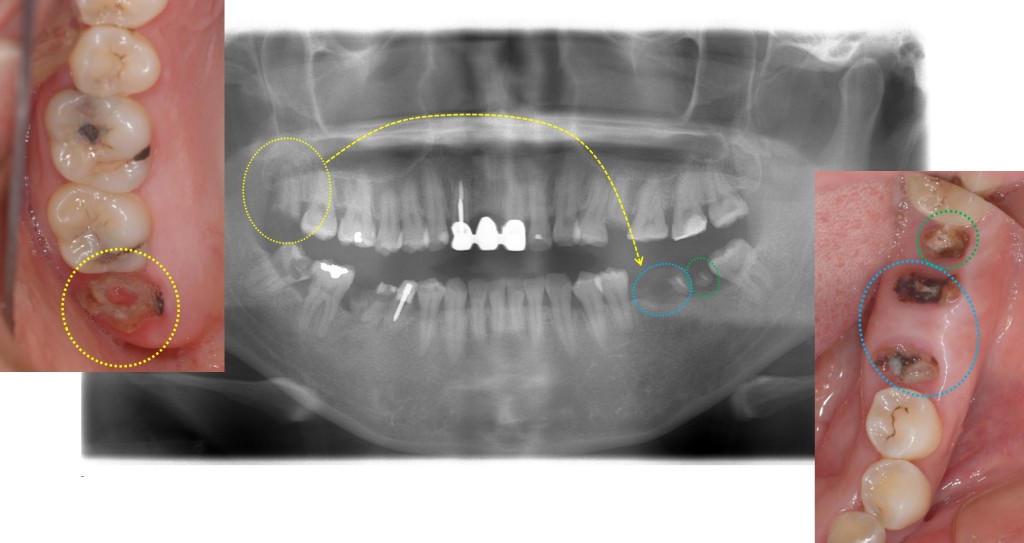

まず下写真からご覧ください。

青〇と緑〇の歯は根だけの状態になっており抜歯する必要があります。

そこで、黄色〇(親知らず)を抜歯して青〇部分に移植する計画としました。